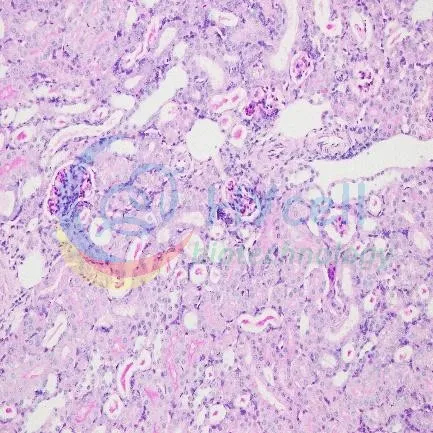

PAS染色

| 正常组 | 模型组 |

PAS染色结果:与正常组相比,模型组基底膜相对增厚,肾小球明显萎缩、腔隙增加,肾小动脉壁略有增厚、管腔变狭窄。